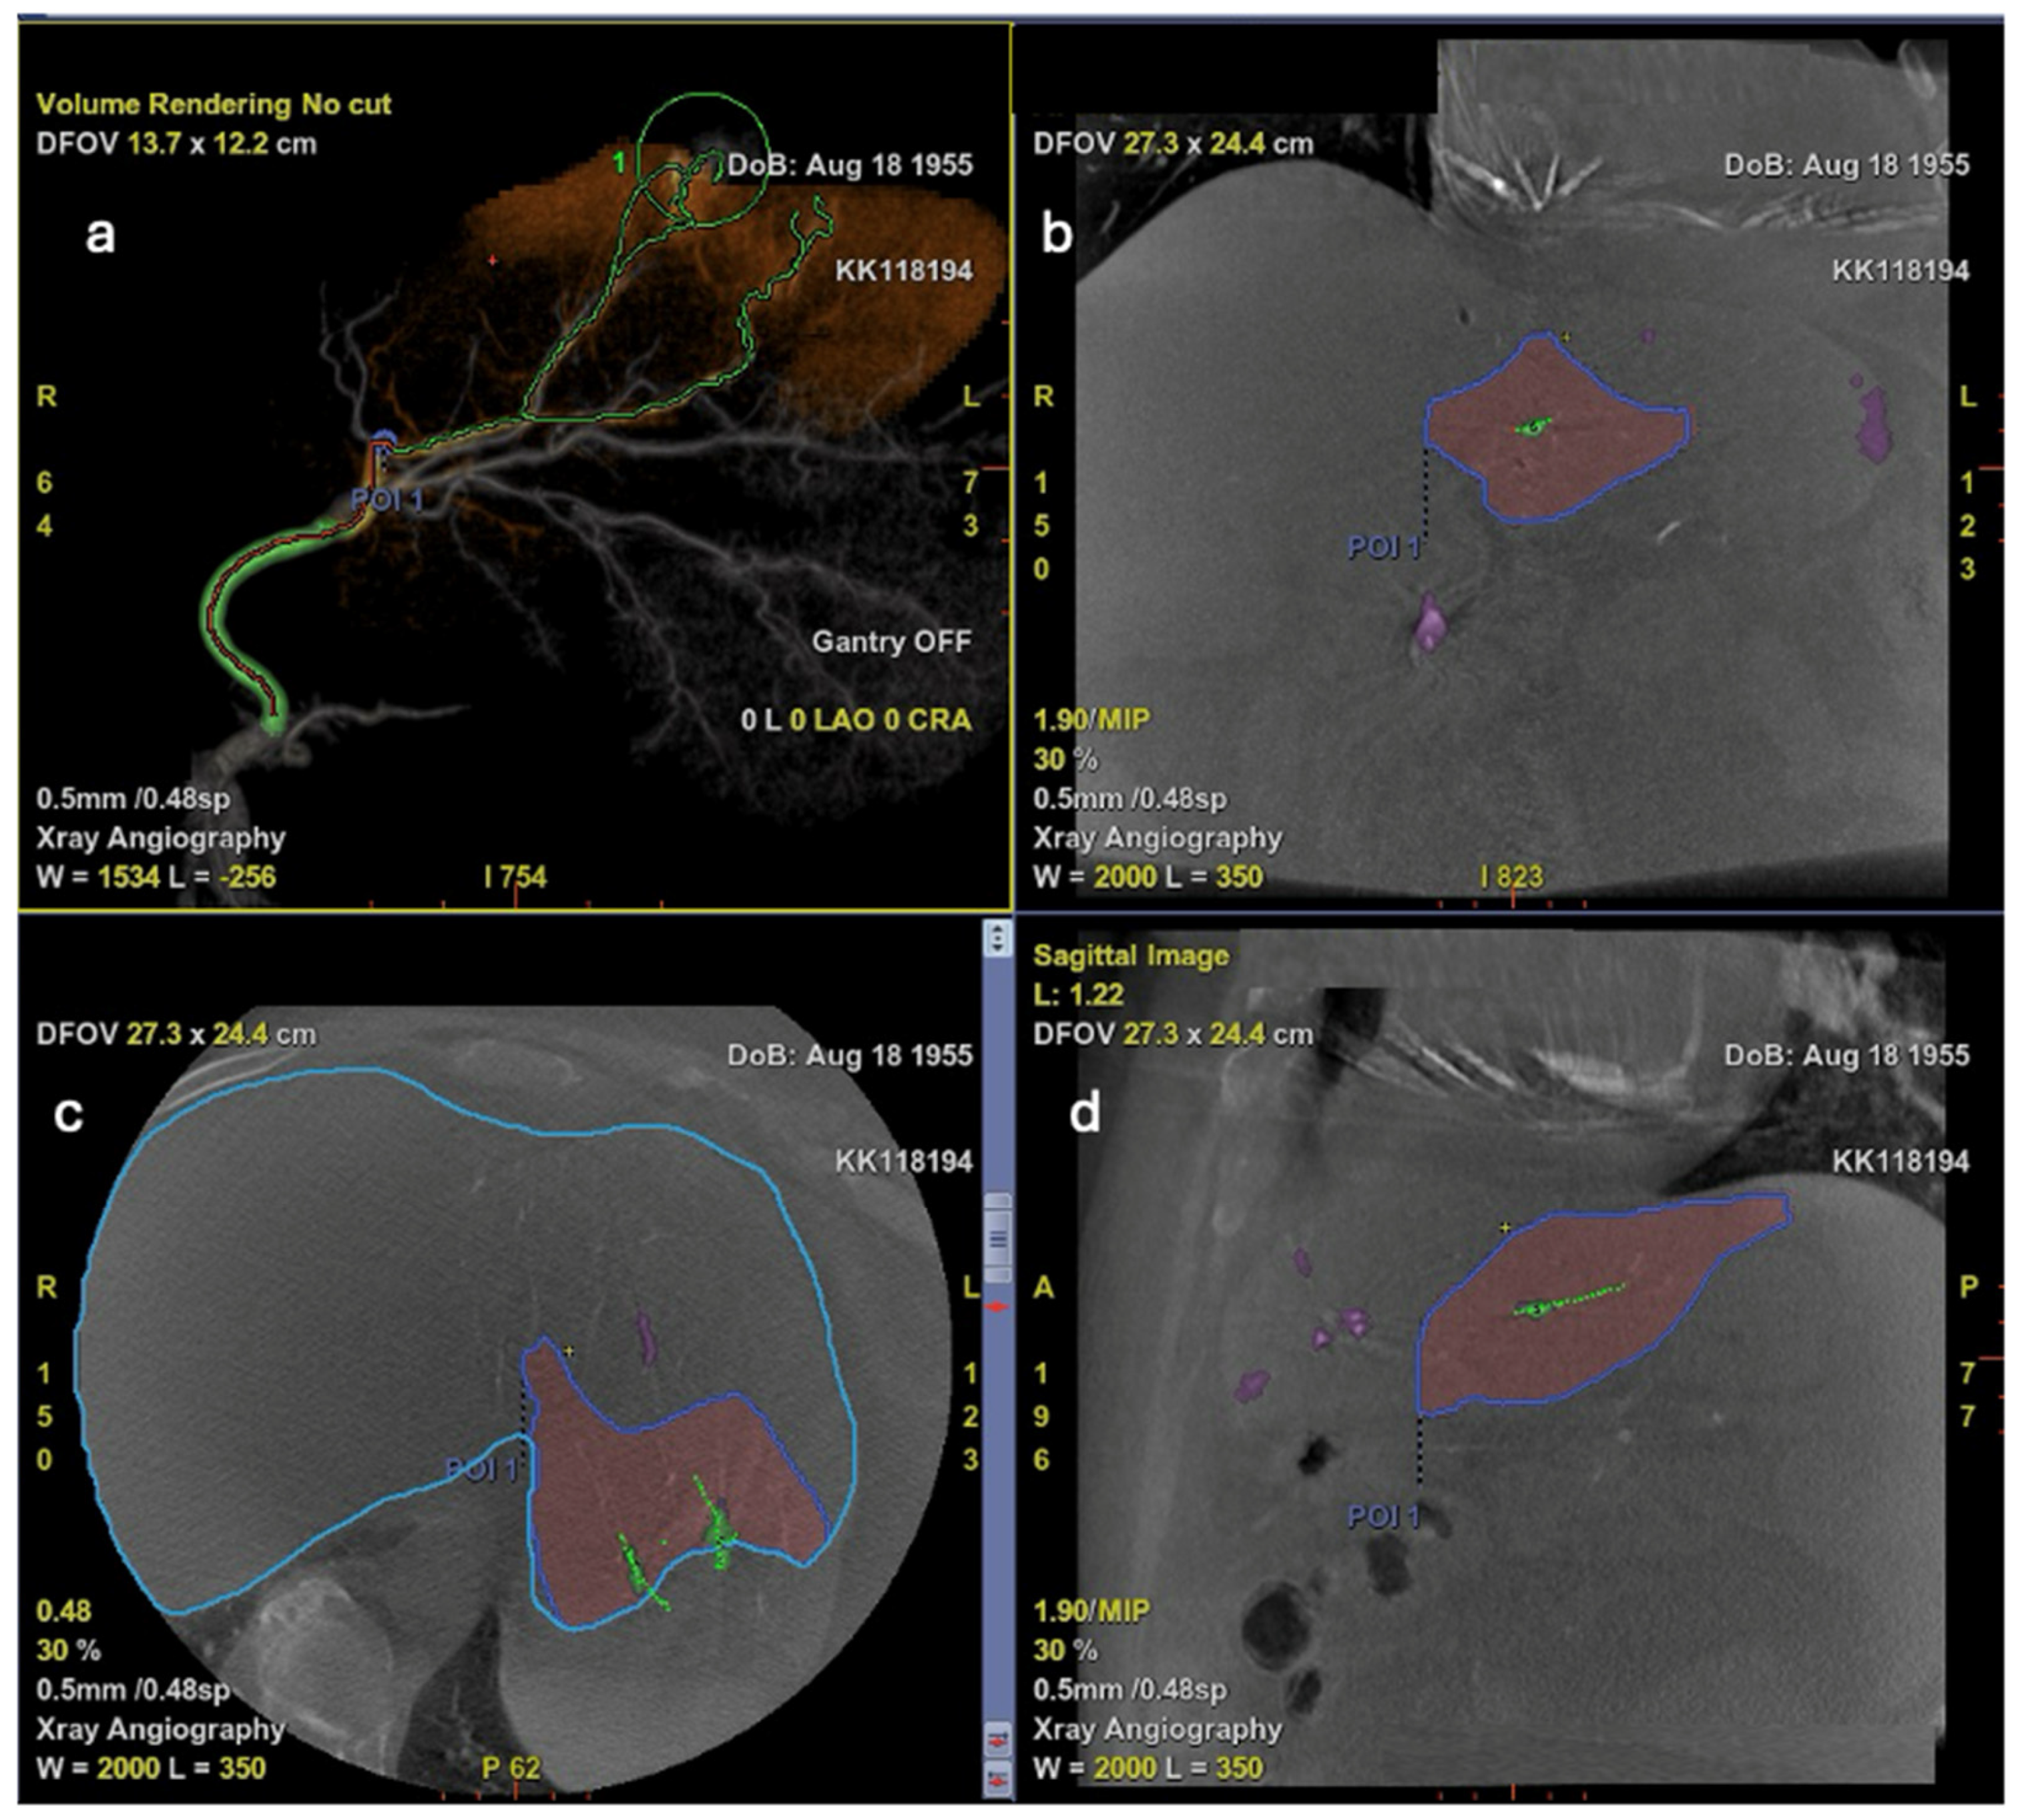

6. Additive Role of Cone-Beam CT

7. Additive Role of Artificial Intelligence

- Automatically extract and reconstruct the hepatic arterial tree;

- Highlight potential tumor feeders, even when overlying vessels obscure direct visualization;

- Provide a “virtual roadmap” for catheter trajectory planning.